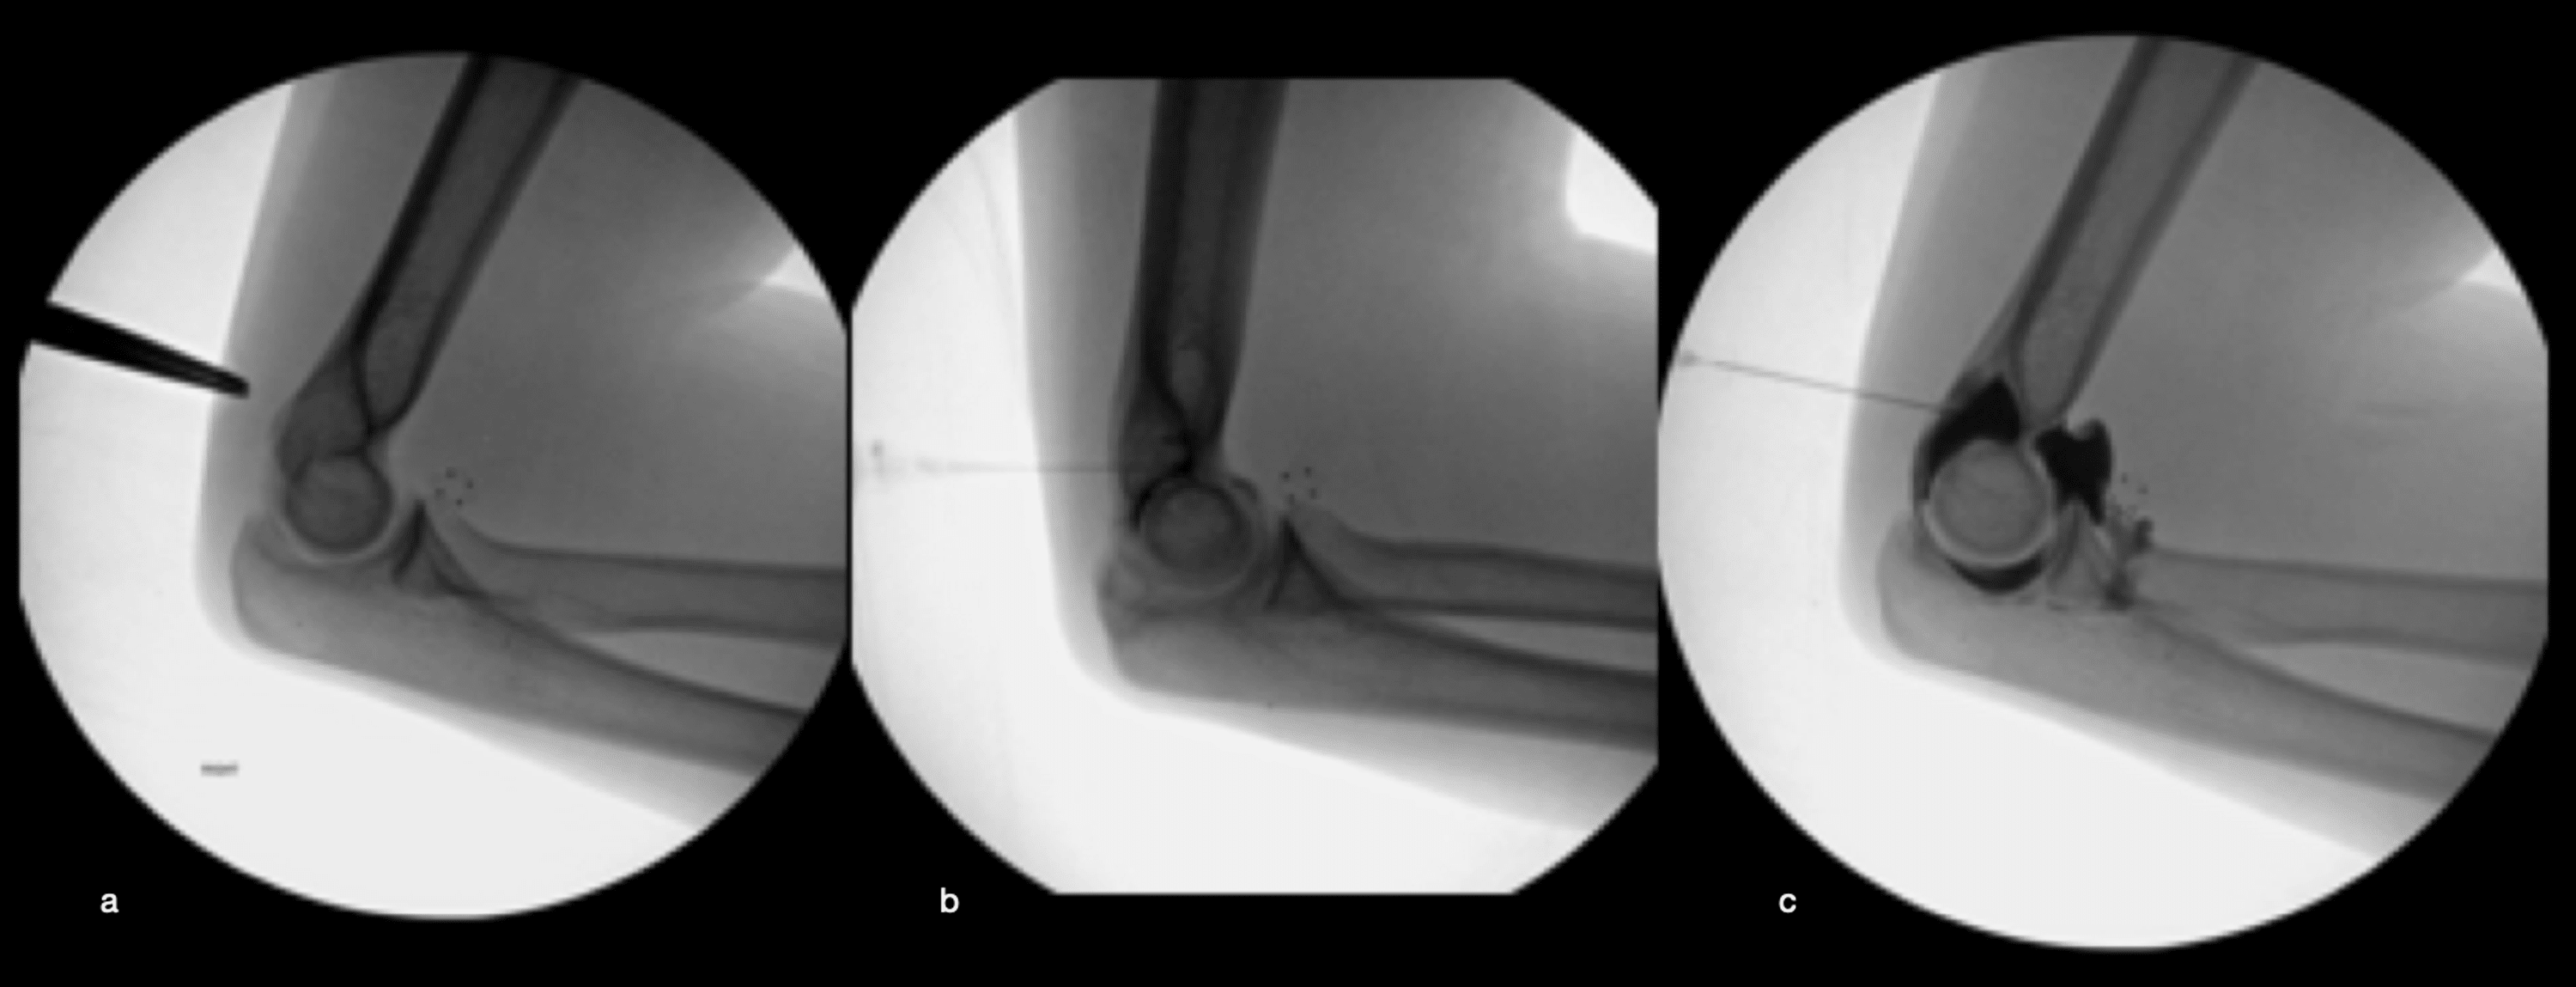

[Figure, Demonstration of positioning and location...] StatPearls Aspiration/Injection Joint arthrocentesis, or joint aspiration, is the clinical procedure performed to diagnose and, in some cases, treat musculoskeletal. The lateral approach is described. It is used to diagnose and treat joint problems, such as arthritis. Joint aspiration is a procedure to remove fluid from the space around a joint. joint aspiration, also called arthrocentesis, is performed when there is. Aspiration/Injection Joint.

Subtalar joint injection through a lateral approach. The provider is Aspiration/Injection Joint The lateral approach is described. arthrocentesis, or joint aspiration, is the clinical procedure performed to diagnose and, in some cases, treat musculoskeletal. It is used to diagnose and treat joint problems, such as arthritis. It is done using a needle and syringe. arthrocentesis, or joint aspiration, uses a needle or syringe to drain fluid from a joint. Joint. Aspiration/Injection Joint.